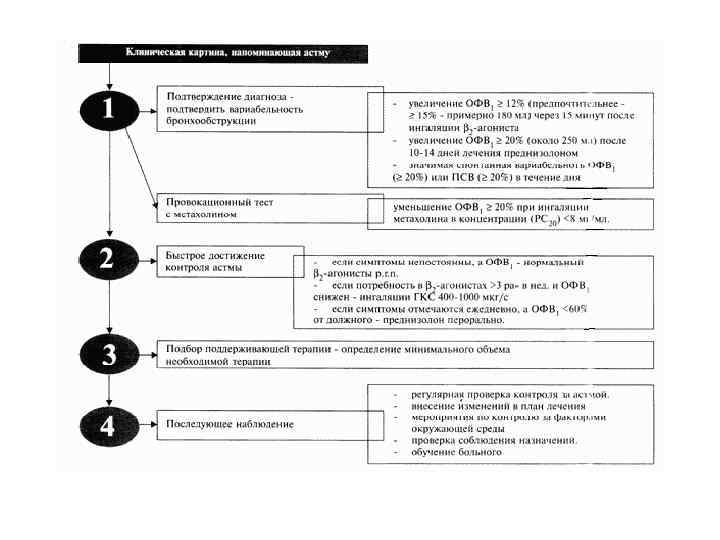

Бронхиальная астма (диагностика болезней).ppt